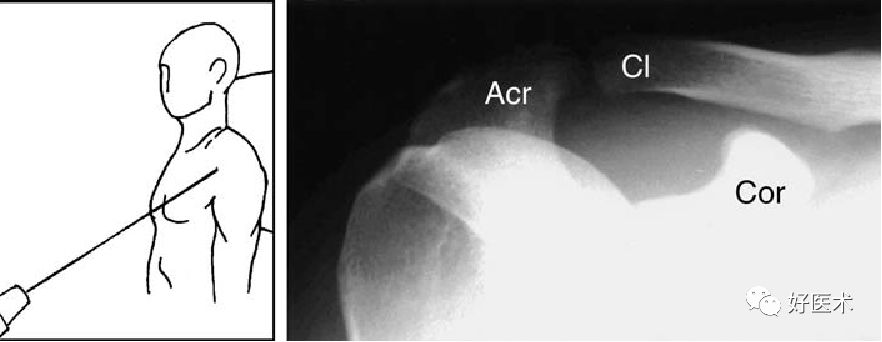

肩关节出口位

-

出口位X线检查使肩胛骨轴位显像。X线正切于“肩胛胸关节”,并且可对肩峰下间隙进行较好的评估

出口位X线片上,可见喙突、肩胛骨体部和肩峰成Y型,肱骨头位于Y型的中心